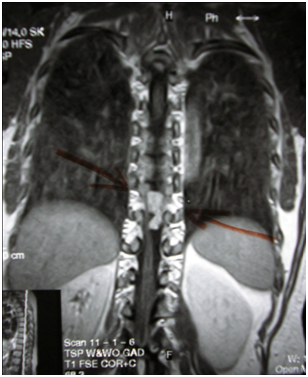

During that same span of time, the patient had yet another prescription for physical therapy from her orthopedic surgeon with a diagnosis of “left ankle and left knee weakness”. Since her objective signs had not changed, on the undersigned recommendation, patient sought the assistance of another neurologist, outside of her home territory. This neurologist requested a magnetic resonance imaging test (MRI), which revealed a mass between T9 and T10 vertebral bodies, located in the intradural extra medullary space of the spine (Figure1 & 2).

Figure 1 Schwannoma at T9-T10, sagittal view.

Figure 2 Schwannoma at T9-T10, frontal view.

- History:A neurosurgeon excised the mass, subsequently diagnosed by a pathologist as a “schwannoma of benign nature” (Figure 3). Following surgery, the patient went home and was wheelchair-bound for three weeks. She walked with a walker for a week and a half, and returned to my office 7 weeks after her surgery.